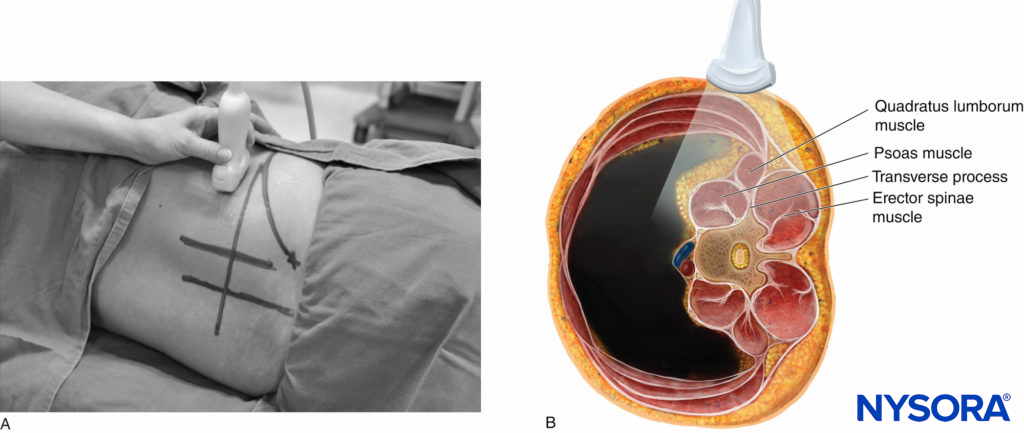

During a PMTOS, the US beam can be insonated either at the level of the transverse process (PMTOS-TP; see Figures 10b and 13 or through the intertransverse space at the level of the articular process (PMTOS-AP: see Figures 10c and 14). Alternatively, a transverse scan can be performed by placing the US transducer more anteriorly in the flank and above the iliac crest (Figures 15, 16, 17, 18, and 19), as described by Sauter and colleagues with the “shamrock method.”

3. The Shamrock Method

Sauter and colleagues recently described an alternative approach for USG LPB, which they refer to as the “shamrock method (Figure 24b).” As described above, a transverse scan is performed at the flank and immediately above the iliac crest, with the patient in the lateral position and with the side to be blocked uppermost (see Figures 15a,b and 24b). Once the sonographic pattern of the “shamrock” is obtained at the level of the L4 transverse process (see Figure 16), the US transducer is tilted slightly caudally until the acoustic shadow of the transverse process is no longer visualized (see Figure 17).